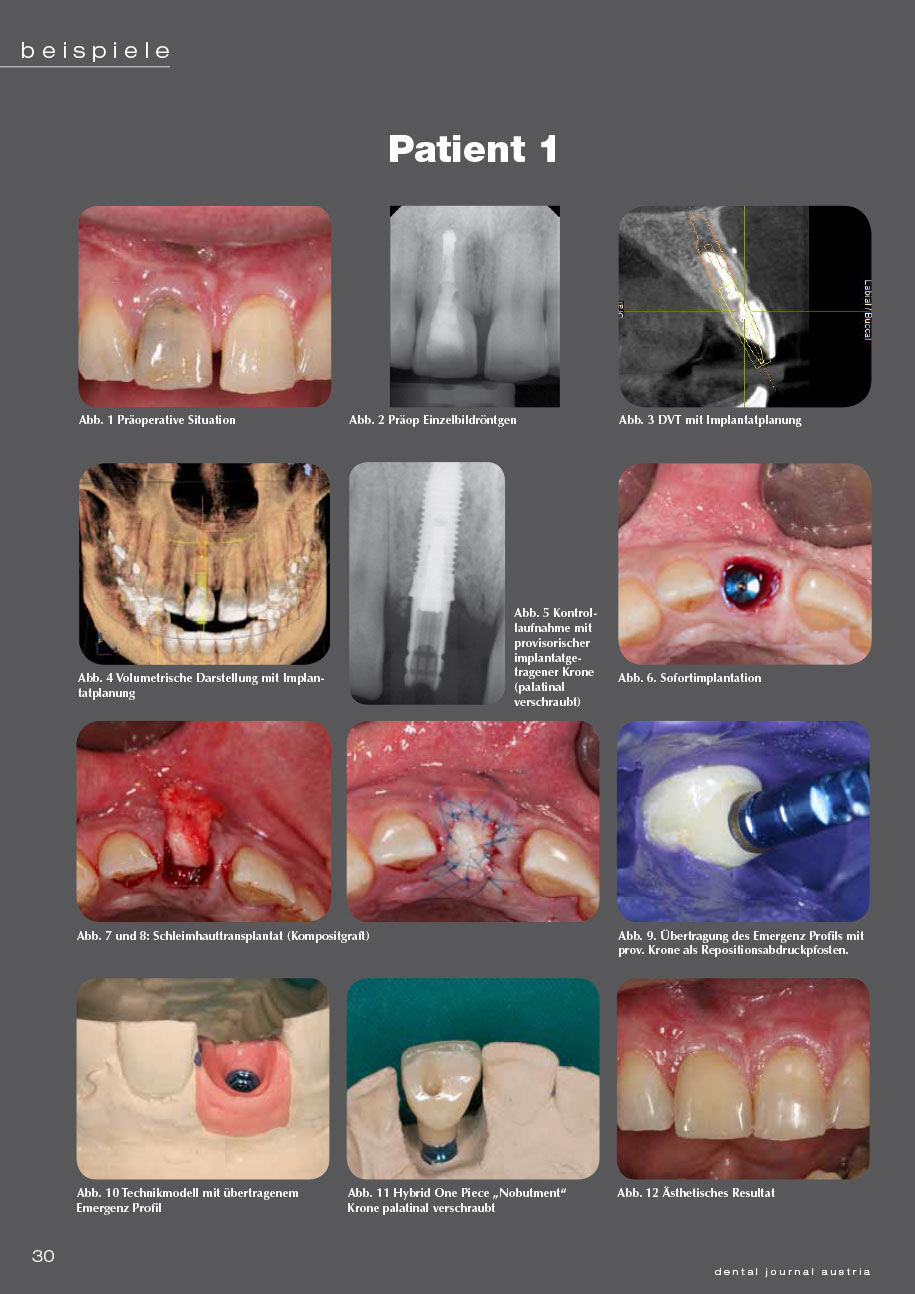

4 Patientenbeispiele